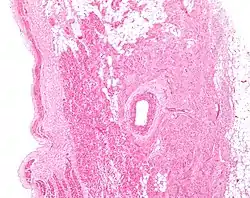

Microanatomy

The cells of the SA node are spread out within a mesh of connective tissue, containing nerves, blood vessels, collagen and fat. Immediately surrounding the SA node cells are paranodal cells.[2] These cells have structures intermediate between that of the SA node cells and the rest of the atrium.[6] The connective tissue, along with the paranodal cells, insulate the SA node from the rest of the atrium, preventing the electrical activity of the atrial cells from affecting the SA node cells.[2] The SA node cells are smaller and paler than the surrounding atrial cells, with the average cell being around 8 micrometers in diameter and 20-30 micrometers in length (1 micrometer= 0.000001 meter).[7] Unlike the atrial cells, SA node cells contain fewer mitochondria and myofibers, as well as a smaller sarcoplasmic reticulum. This means that the SA node cells are less equipped to contract compared to the atrial and ventricular cells.[8]

Action potentials pass from one cardiac cell to the next through pores known as gap junctions. These gap junctions are made of proteins called connexins. There are fewer gap junctions within the SA node and they are smaller in size. This is again important in insulating the SA node from the surrounding atrial cells.[2][8]